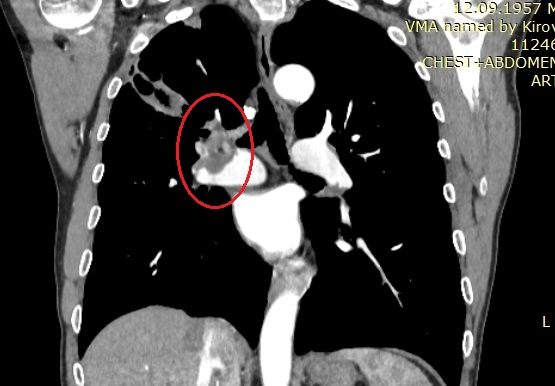

Приангио-КТ груди, живота, малого таза от 3.09.2020 — КТ-картина эмболии правой легочной артерии и ее ветвей, инфильтрат в S2 правого легкого с наличием полостей деструкции в структуре, участки консолидации легочной ткани в S1, S2, S3 правого легкого, один из которых с полостью деструкции с учетом наличия тромботических масс в артериях А1, А2, А3 справа более вероятно соответствует инфаркт-пневмонии с полостями деструкции (рис. 2, 3). КТ-картина образований правой почки — с наличием неоднородных тромботических масс в правой почечной вене, НПВ (опухолевого генеза), омываемых со всех сторон.

Рис. 3. КТ-ангиограмма груди пациента Г. Красными стрелками указана зона деструктивной инфаркт-пневмонии верхней доли правого легкого.